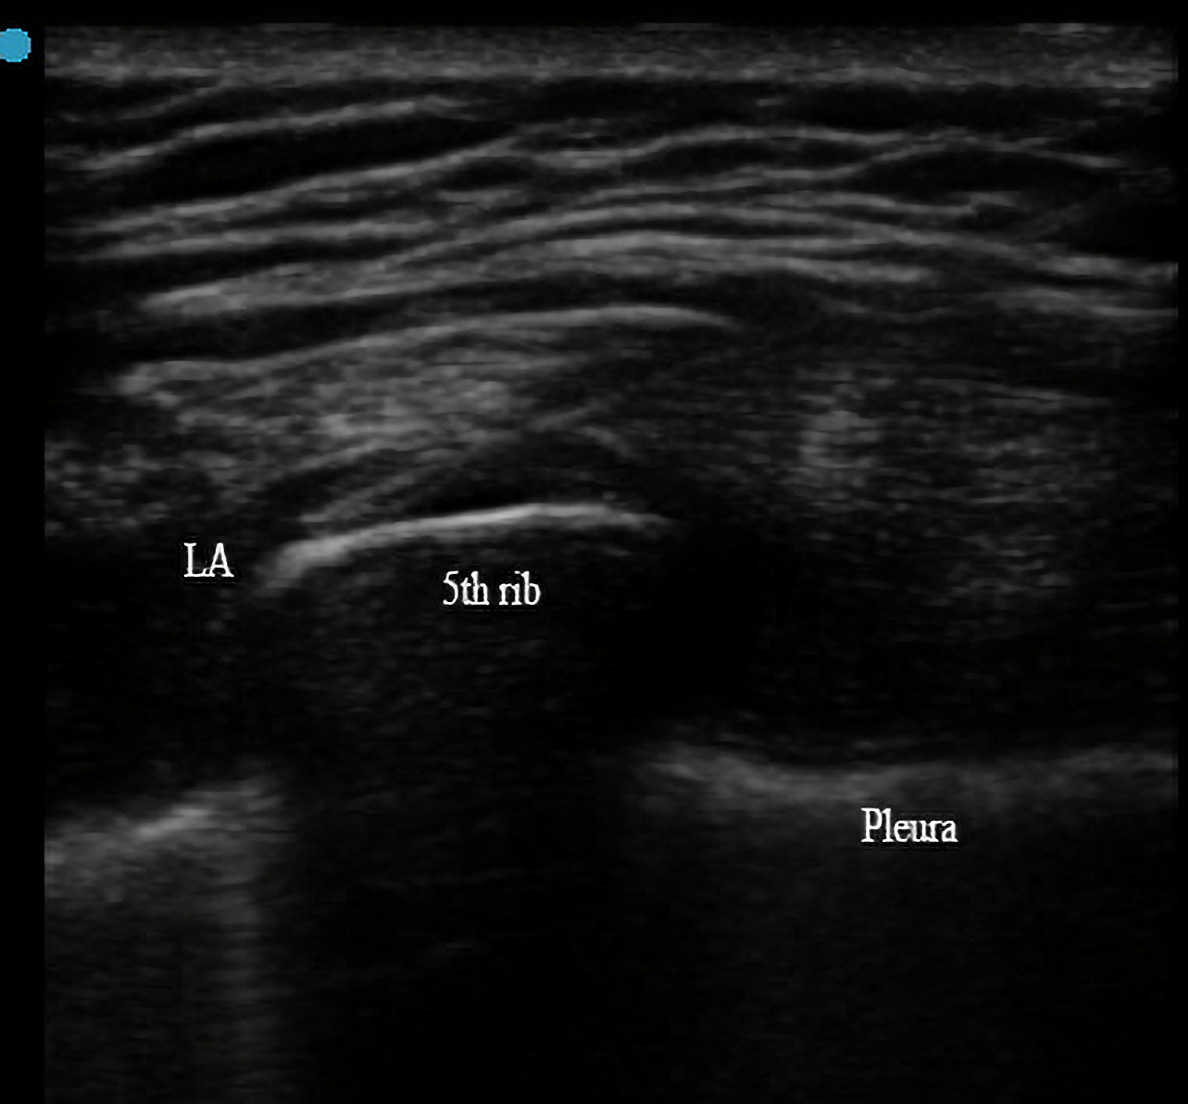

Methods: After chest incision closure was complete, all patients underwent ultrasound-guided SAPB with catheter insertion. Numerical rating scale (NRS), additional opioid consumption, time to endotracheal tube removal, ICU length of stay, and catheter-related adverse events were followed up and recorded for each patient within one week after the procedure.